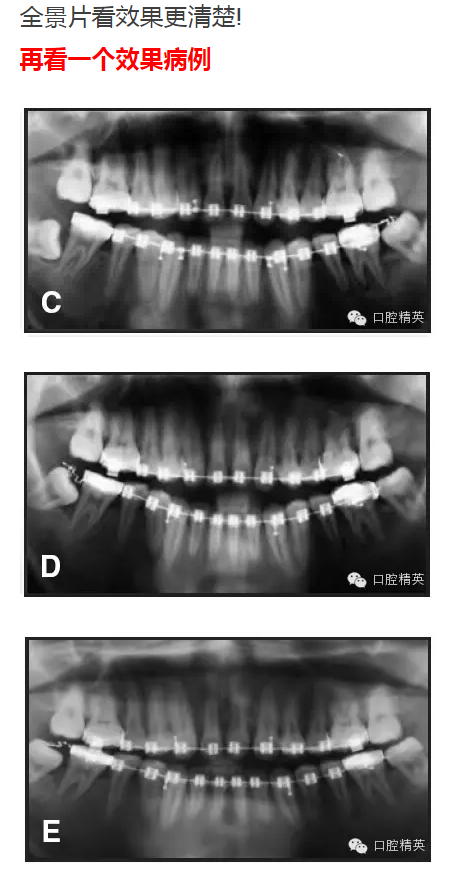

強(qiáng)烈推薦一種糾正傾斜磨牙的方法